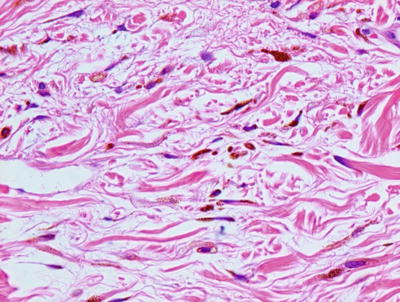

Histologic findings consist of a loose aggregation of densely pigmented, dendritic-shaped melanocytes within the superficial portion of the reticular dermis (Figs. 20.17 and 20.18). There is no intraepidermal melanocytic proliferation. Cytologic atypia and mitotic activity are not present, and the melanocytes tend to course as single cells and do not form nests. The histologic changes are indistinguishable from those of nevus of Ota, and the distinction is made based on the affected body site [73].

Fig. 20.17

Sparse numbers of densely pigmented spindled melanocytes are present in the superficial dermis in nevus of Ito. The epidermis is unremarkable

Fig. 20.18

Spindled melanocytes and melanophages course individually between reticular dermal collagen bundles in nevus of Ito